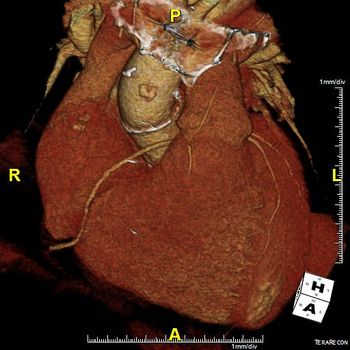

Image IQ: 74-year-old, History of Aortic Valve RepairByDuke Duncan, MDApril 17th 201574-year-old with history of aortic valve repair at an outside hospital.

Image IQ: 85-year-old Male, History of Aortic Stenosis ByDuke Duncan, MDApril 2nd 201585-year-old male with history of aortic stenosis receiving contrast-enhanced CT for preoperative evaluation.